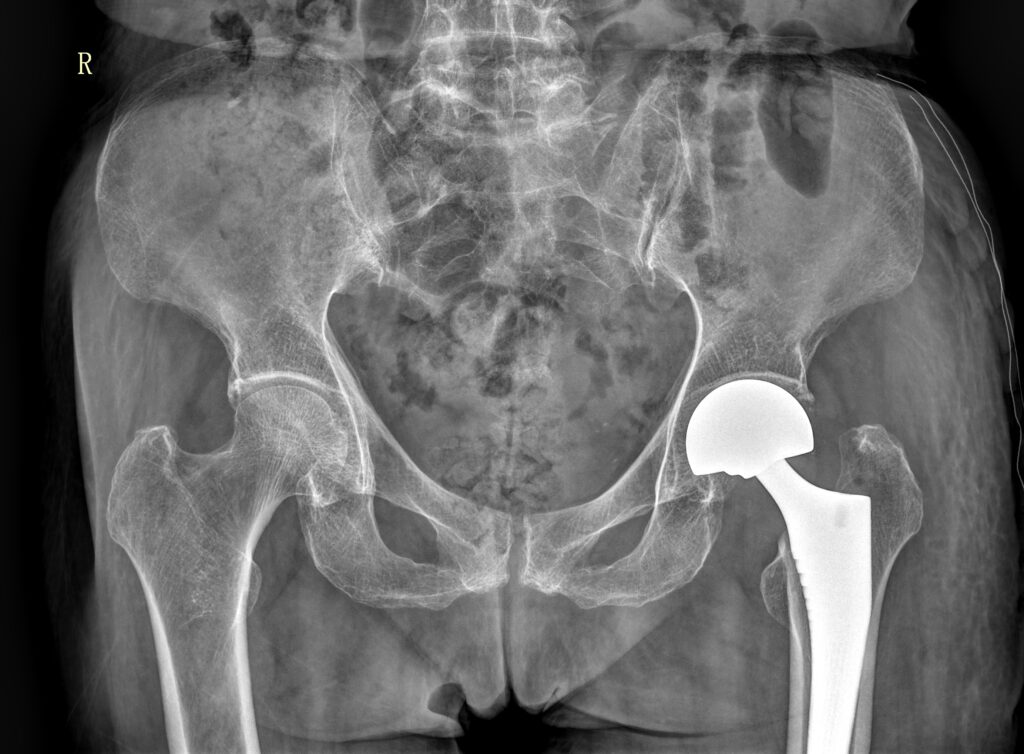

股骨颈骨折人工股骨头置换术(Artificial femoral head replacement for femoral neck fractures)